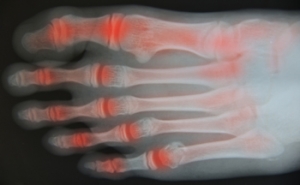

A broken toe can occur when it is jammed into a piece of furniture, or if a heavy object is dropped on it. It can cause severe pain and discomfort, and it may become difficult to walk. There are noticeable symptoms that often occur with a broken toe, including swelling, bruising, and the toe may appear red. In severe toe fractures, the fractured bone may protrude from the toe. This requires immediate medical attention in order to accelerate the healing process, and possibly prevent an infection from occurring. Buddy taping is an effective strategy that is used to stabilize the broken toe. This is done by taping the toe to the toe next to it, and it may provide ease in accomplishing daily activities. Swelling may be reduced when the leg is elevated, and over the counter medications are taken for pain. If you have endured a broken toe, it is suggested that you speak to a podiatrist as quickly as possible who can guide you toward correct treatment.

Although most people try to avoid foot trauma such as banging, stubbing, or dropping heavy objects on their feet, the unfortunate fact is that it is a common occurrence. Given the fact that toes are positioned in front of the feet, they typically sustain the brunt of such trauma. When trauma occurs to a toe, the result can be a painful break (fracture).

Trauma to the foot, especially the toes, can occur in many ways. Banging them, stubbing them, or dropping something on them are a few different ways this trauma can occur. Given the fact that toes are positioned in front of the feet, they typically sustain the brunt of such trauma. When trauma occurs to a toe, the result can be a painful break or fracture. Another type of trauma that can break a toe is repeated activity that places stress on the toe for prolonged periods of time.

Broken toes can be categorized as either minor or severe fractures. Symptoms of minor toe fractures include throbbing pain, swelling, bruising on the skin and toenail, and the inability to move the toe with ease. Severe toe fractures require medical attention and are indicated when the broken toe appears crooked or disfigured, when there is tingling or numbness in the toe, or when there is an open, bleeding wound present on the toe.

Generally, a minor toe break will heal without long-term complications. However, it is important to discontinue activities that put pressure on the toe. It is best to stay off of the injured toe and immediately get a splint or cast to prevent any more additional movement of the toe bones. You can also immobilize your toe by placing a small cotton ball between the injured toe and the toe beside it. Then, tape the two toes together with medical tape. Swelling can be alleviated by placing an ice pack on the broken toe directly as well as elevating your feet above your head.

Severe toe fractures may be treated with a splint, cast, and in some cases, minor surgery, especially when the big toe has been broken. Due to its position and the pressure the big toe endures with daily activity, future complications can occur if it is not properly treated. Pain associated with minor toe fractures can be managed with over-the-counter pain medications. Prescription pain killers may be necessary for severe toe fractures.

The healing time for a broken toe is approximately four to six weeks. In severe cases where the toe becomes infected or requires surgery, healing time can take up to eight weeks or more. While complications associated with a broken toe are immediately apparent, it is important to note that there are rare cases when additional complications, such as osteoarthritis, can develop over time. You should immediately speak with your podiatrist if you think you have broken your toe due to trauma. They will be able to diagnose the injury and recommend the appropriate treatment options.